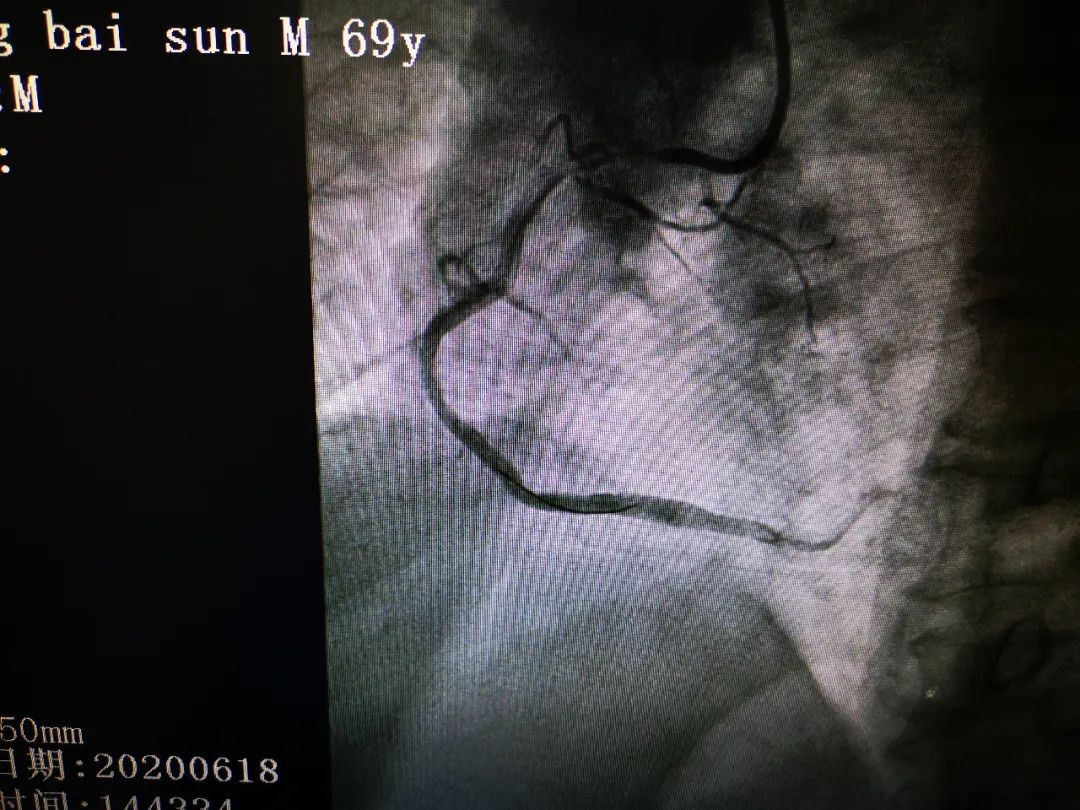

13 时 56 分,行选择性冠脉造影,造影结果显示:前降支中段狭窄 99%,回旋支中段慢性闭塞,右冠近中段急性闭塞,TIMI 血流 0 级。患者冠状动脉三支主要血管均有严重病变,心脏血流灌注突然中断,极易发生恶性心律失常、心脏骤停,死亡风险极高,这让正在手术的吕学祥主任心头一紧,「立即开通右冠,恢复冠脉血流」吕主任当机立断做出了手术指示。

14 时 43 分,经过团队的不懈努力,手术成功完成,再次行冠脉造影确认患者急性闭塞的血管已经开通,血流完全恢复,生命体征也平稳下来,主任们这才松了口气,直到此时才发现,所有参与抢救的医生手术衣均已湿透。